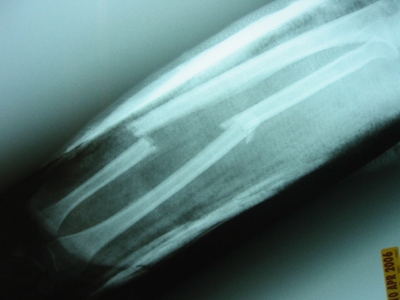

- "Both-bone" forearm fractures

- Descriptive

- closed versus open

- location

- comminuted, segmental, multifragmented

- displacement

- angulation

- rotational alignment

- Radiographs

- recommended views

- AP and lateral views of the forearm